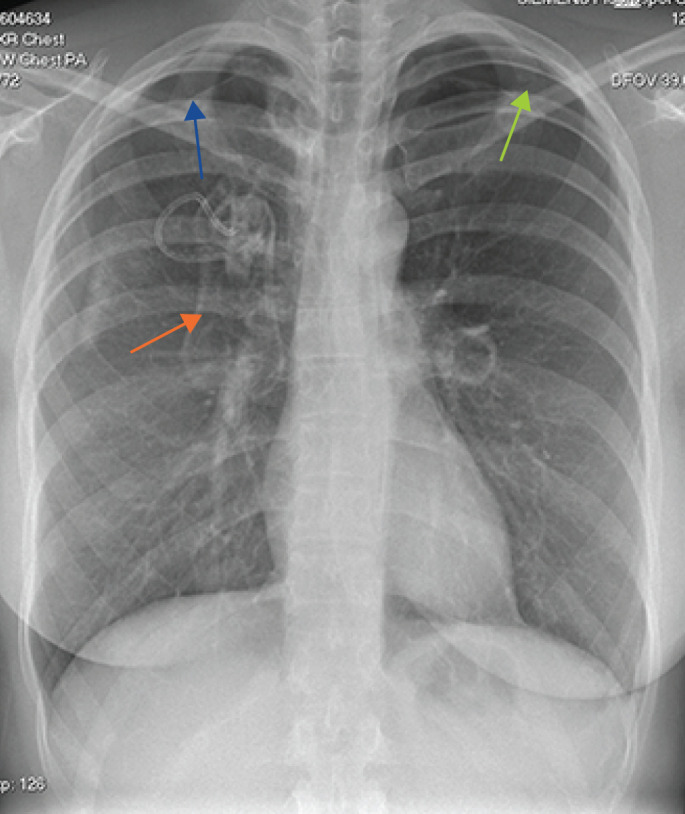

One of the respiratory complications of rheumatoid arthritis (RA) is formation of lung nodules, which can rupture to cause pneumothoraces. We present a case of recurrent pneumothoraces due to accelerated RA nodulosis, secondary to biologic therapy. https://bit.ly/3WBhgOe.

Abstract Image